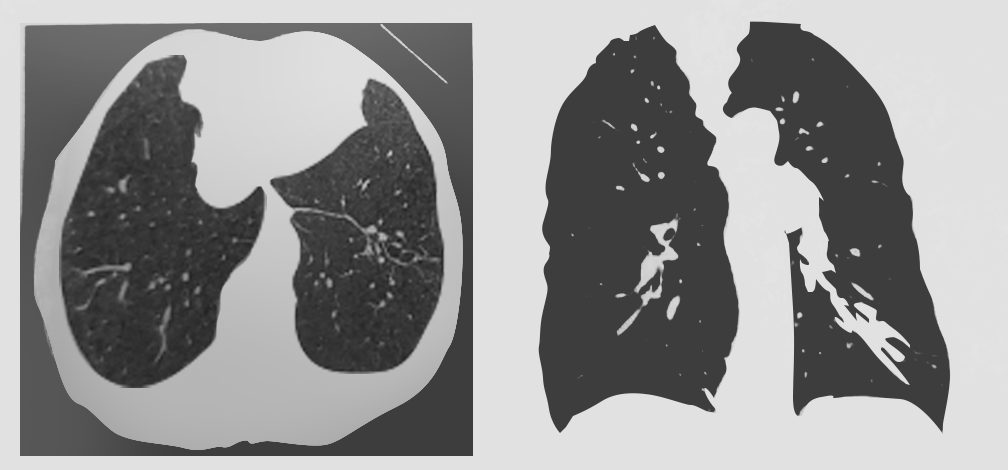

患者,男,55岁,反复咳嗽、咯痰、咯血10余年,咯大量黄色黏液痰一周,发现痰中带血3天。无发热,胸痛,气喘等。有长期吸烟史。今晨患者无明显诱因剧烈咳嗽,咯血1次,量约100ml,鲜红色。来院就诊,胸部CT示:左下肺支气管柱状及囊状病变,支气管壁增厚(如图1)。为进一步诊治收住院。

图1